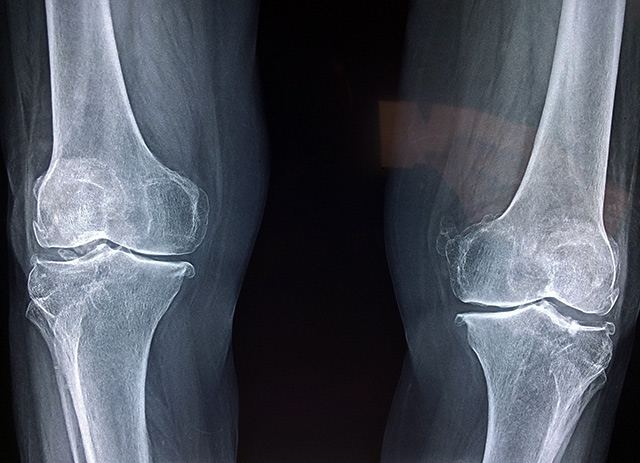

x-ray of the knees Equipment required: X-ray machines, peripheral DXA machines, Quantitative Computed Tomography and Ultrasounds are the different methods on how to scan bone density.